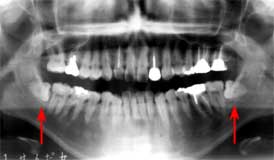

初診時 パノラマ 術後3年 パノラマ

年齢の割に歯槽骨の吸収が著しい

34歳 女性

右の上下智歯にカリエス発生

主訴は、歯周疾患治療の希望。

初診時口腔内およびX線所見:

口腔清掃状態は比較的良好であったが、歯肉縁下の歯石沈着が著明。また、年齢の割に 歯槽骨の吸収が著しく将来に大きな不安を抱える状態であった。

処置および経過:

「5は抜歯とし、7-|-3に対しては歯周外科処置(Fop+レーザーによる根面処理) を施行することとした。歯周初期治療と並行して補綴予定部位の根管処置を行い歯牙保存に 務めた。

一連の歯周処置と補綴処置を終えメインテナンスに移行して順調に経過していたように 思われたが、レントゲンを撮って始めてカリエスの存在に気づいた

考察:

メインテナンス時には必ず脱離やカリエスのチェックを行っていた積もりですが、カリエスの 存在に全く気がつきませんでした。まだ何とかなる時点での発見に安堵する反面、それまで 気がつかなかったことに情けない思いを抱いています。智歯であるが故に発見が遅れたと いうのは言い訳、智歯であるからこそもっと注意しておくべきでした。

感想:

3年でこれだけのカリエスはちょっと異例です。気の緩みがあったわけではありませんが ショックは大きい!!